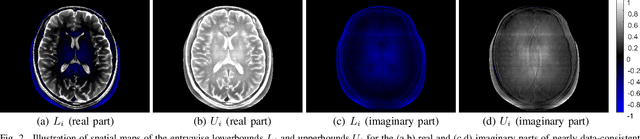

Abstract:Ill-posed linear inverse problems appear frequently in various signal processing applications. It can be very useful to have theoretical characterizations that quantify the level of ill-posedness for a given inverse problem and the degree of ambiguity that may exist about its solution. Traditional measures of ill-posedness, such as the condition number of a matrix, provide characterizations that are global in nature. While such characterizations can be powerful, they can also fail to provide full insight into situations where certain entries of the solution vector are more or less ambiguous than others. In this work, we derive novel theoretical lower- and upper-bounds that apply to individual entries of the solution vector, and are valid for all potential solution vectors that are nearly data-consistent. These bounds are agnostic to the noise statistics and the specific method used to solve the inverse problem, and are also shown to be tight. In addition, our results also lead us to introduce an entrywise version of the traditional condition number, which provides a substantially more nuanced characterization of scenarios where certain elements of the solution vector are less sensitive to perturbations than others. Our results are illustrated in an application to magnetic resonance imaging reconstruction, and we include discussions of practical computation methods for large-scale inverse problems, connections between our new theory and the traditional Cram\'{e}r-Rao bound under statistical modeling assumptions, and potential extensions to cases involving constraints beyond just data-consistency.